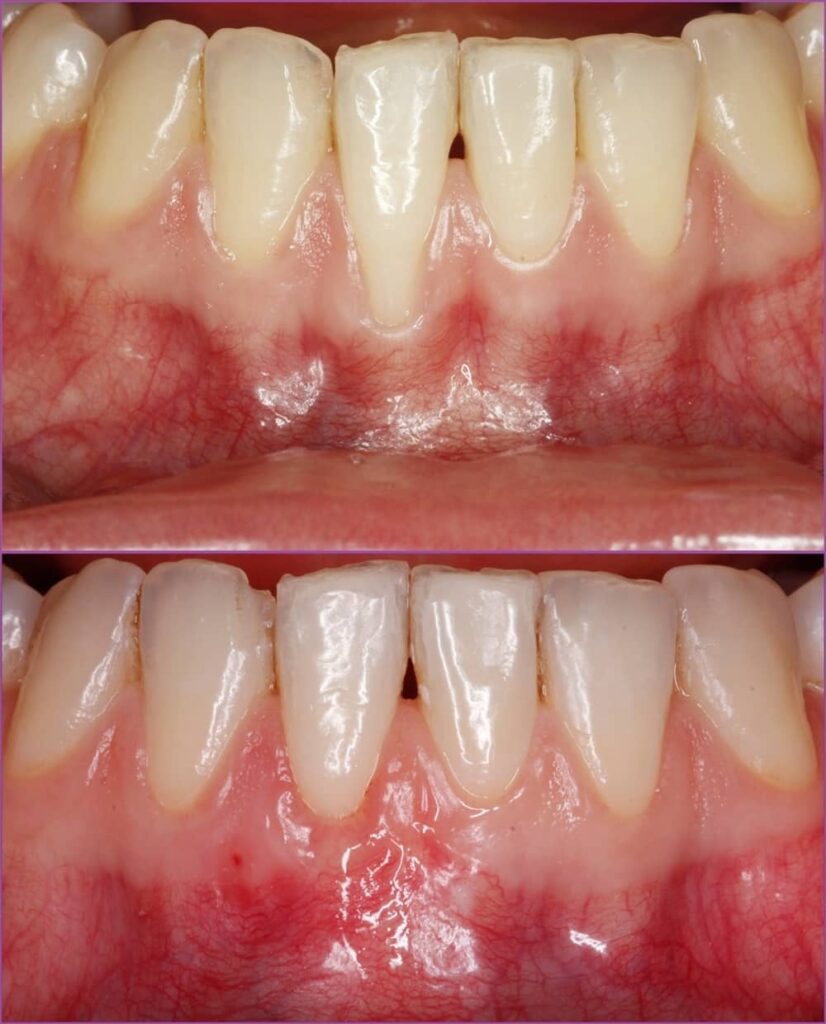

Így hát nem csoda, hogy sikerült az ínyt közel tökéletes pozícióba visszaépíteni és a fognyaki érzékenység is nagymértékben javult. A hölgy rendkívül elégedett volt az elért eredménnyel.